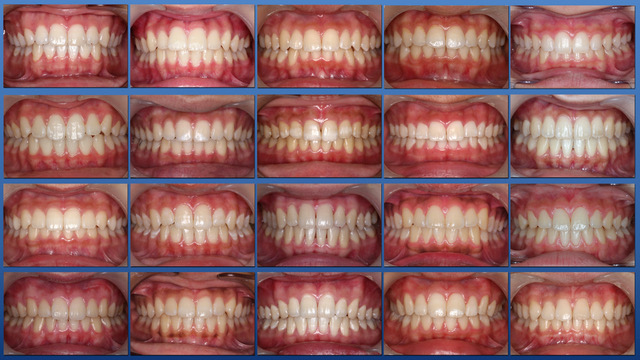

須貝歯科医院には小児の患者さんが多く来院していますがほとんどが虫歯の予防と歯ならび管理の患者さんで虫歯の治療が必要な場合は稀です。4カ月ごとの定期健診を小さい頃から受けることによって虫歯の予防ができ永久歯列が完成する12才時の一人虫歯経験歯数の平均は約0.8本で世界一のスウェーデンより高い水準になっています。

日本の平均の2.4本とは比べものになりません。また乳歯から永久歯への生え替わりを注意してみていくことで多くの歯列不正は予防でき、その経験も豊富です。

定期健診を継続し、虫歯に一回もなったことのない歯並びのきれいな患者さんが多く育っています。

子供達を健康で綺麗な歯並びの永久歯列に誘導していくことを咬合育成と言います。開業時から来院していた子供達を見ていて、どうしたら綺麗な歯並びにできるのかを研究してきました。最近その成果が上がるようになり多くの子供達が健康できれいな歯並びをもった大人になって来院するようになっています。対外的にも「講演・論文」のページにあるように各地の歯科大学や歯科医師会からその分野の講演を依頼されるようになり、いつのまにか須貝歯科医院の得意分野になってしまいました。永久歯への生え替わりの時期が最も重要な時期です。簡単な装置で歯並びを改善していくのですが患者さんによっては矯正専門医に紹介しなければならないケースもあります。その時は地元の信頼できる矯正専門医をご紹介しています。

上の前歯は下の前歯より前にないといけませんが、前歯の生え替わりの時に1本逆に生えてきました。そのままではきれいな歯並びにはなりそうもありません。この時が治療のタイミングです。簡単な矯正装置で改善しただけでその後きれいな永久歯列になりました。